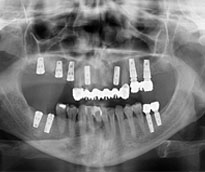

Ýmplant

Protezler